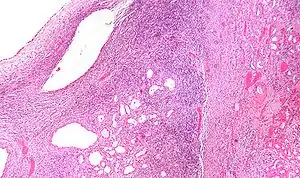

| Micrograph of a cystic nephroma (left of image). Normal kidney is seen on the right. H&E stain. | |

Micrograph of a cystic nephroma. H&E stain.